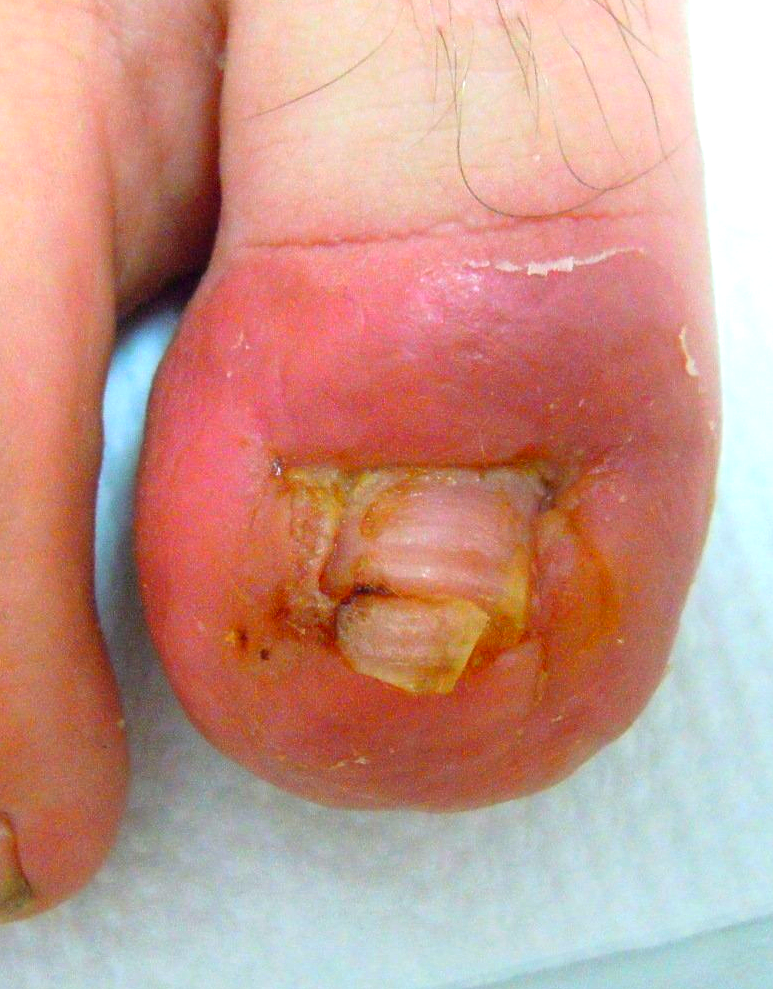

1.) Akutfall am Nagel

👉 Im Folgenden ein Akutfall der besonderen Art:

Kommt nicht sehr oft aber doch immer wieder einmal vor.

🔴 Der Nagelspan kommt bereits DURCH das Weichgewebe.

In Vergrößerung am Monitor auf Bild 2

🔴Bild 3: der geborgene Nagelspan Bild 4: in dieser Position grub sich der Nagel durch das Gewebe